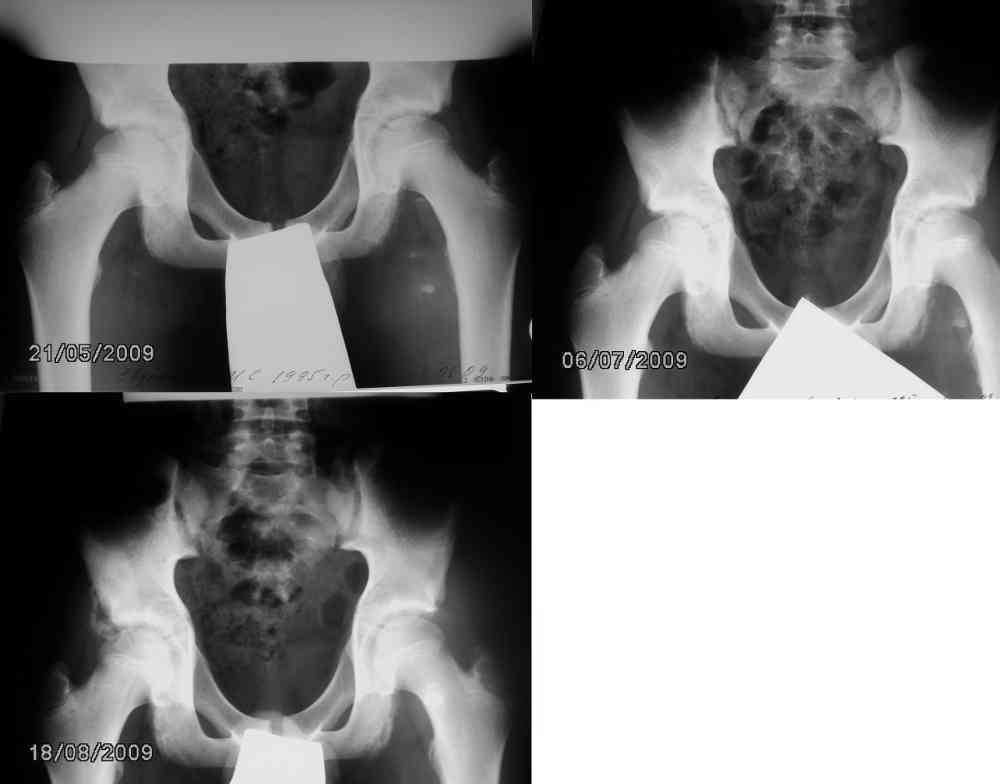

Уважаемые травматологи , хотелось бы услышать ваше мнение. Я – врач-рентгенолог. Пациент – мой сын. На данный момент ребенку 14 лет. Мальчик занимается легкой атлетикой. Первые жалобы год назад. Появились боли в левом бедре без ограничения подвижности. В течении месяца боль мигрировала в область левого седалищного бугра. На рентгенограмме костей таза от 21.05.09 нечеткость контура левого седалищного бугра. Идет диф диагноз между новообразованием и остеохондропатией. На КТ данных за объёмный процесс нет. Контрольный снимок через 1,5 мес от 06.07.09 признаки формирования контура апофиза. Боли практически перестали беспокоить. Следующий контрольный снимок 18.08.2009 – апофиз левого седалищного бугра уже не вызывает особых беспокойств, но как объяснить появление фрагментированного участка по латеральному контуру тела правой седалищной кости. Вновь диф диагноз между новообразованием и остеохондропатией (в середине июля был неубедительный факт травмы - пнул мяч, появилась боль в правой паховой области). Клинические проявления на момент проведения исследования скудные: незначительная болезненность при напряжении мышц передней поверхности правого бедра. Пальпаторно определяется небольшой участок уплотнения в паховой области, практически безболезненный. Назначается повторное КТ . Заключение : больше данных за остеохондропатию тела подвздошной кости. На данный момент (март 2010) мальчик жалоб не предъявляет. Пальпируемый фокус уплотнения уменьшился. Травматолог настаивает на проведении повторного, уже третьего за год КТ, либо проведении биопсии. Я, как рентгенолог, понимаю, что это очень большая доза для ребенка, тем более зона интереса неудачная. Мальчик получил уже 30мЗв, при норме 1 мЗв в год. Уважаемые травматологи, пожалуйста, озвучьте свои мнения, и хотелось бы узнать какой прогноз.Заранее СПАСИБО!

Светлана, не мучайте ребенка! У мальчика перегрузочная болезнь - функциональная перестройка бугра седалищной кости в месте прикрепления мышц - у юнных спортсменов встречается довольно часто. Ограничить нагрузки - пройдет само. Сделайте цифровой снимок через 6 мес., если не будет ухудшения состояния.

Здравствуйте. По поводу левого седалищного бугра я , пожалуй, соглашусь. А вот по латеральному контуру тела ПРАВОЙ ПОДВЗДОШНОЙ кости что??? Почему - то на всех форумах акцент ставится на седалищный бугор, а что фрагментация справа - вариант нормы?

Ув. Светлана , у вашего ребенка в области еседалищной кости процесс, аналогичный болезни Осгуда-Шлятера на бугристоти б/берцовой кости, уменьшить нагрузки, вырастет, все пройдет.